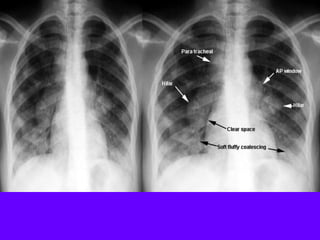

Diffuse Alveolar Pneumonia

The most common causes for diffuse alveolar pneumonia are:

Pneumocystis

Cytomegalovirus